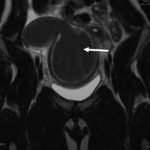

Due to pain out of proportion to her exam, an ultrasound of her pelvis was obtained and showed a blood-filled distended uterus, or hematometrocolpos (white arrow), with a 4.9 cm right ovarian cyst (blue arrow). A pelvic magnetic resonance imaging (MRI) then revealed an obstructed right hemi-vagina, normal left uterus and vagina and ipsilateral renal agenesis (red arrow) with normal left kidney (double arrow) consistent with obstructed hemivagina, ipsilateral renal agenesis (OHVIRA) syndrome. The patient underwent surgical repair with complete resolution of symptoms.